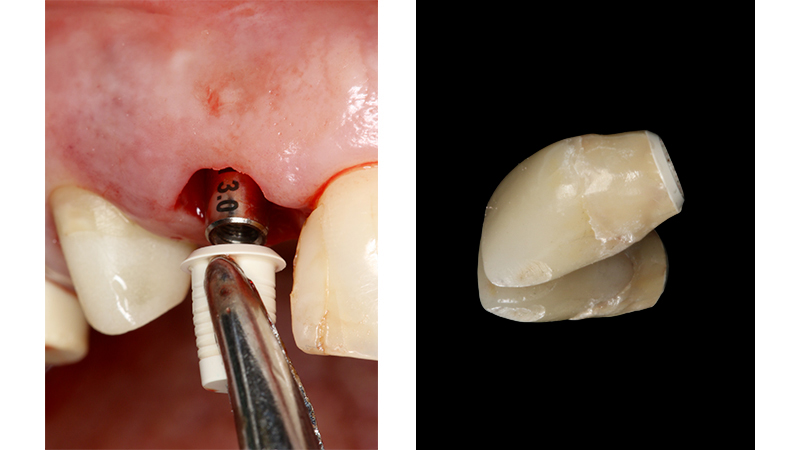

Sul 12 veniva eseguito un impianto post-estrattivo con carico immediato mediante moncone conometrico e provvisorio ricavato ribasando una cappetta provvisoria in peek e applicazione a frizione mediante conometria (Figs. 19, 20, 21, 22, 23).

Carico immediato su 12 con moncone conometrico dritto e cappetta provvisoria in peek ribasata in resina su provvisorio. Foto dopo l'intervento con esecuzione flapless e leggera plastica gengivale del Tuber applicazione di cappette di guarigione in peek. Guarigione dei tessuti dopo 3 mesi e impronta digitale definitiva per finalizzare il caso

Fig. 19, 20 - Carico immediato su 12 con moncone conometrico dritto e cappetta provvisoria in peek ribasata in resina su provvisorio. Foto dopo l'intervento con esecuzione flapless e leggera plastica gengivale del Tuber applicazione di cappette di guarigione in peek. Guarigione dei tessuti dopo 3 mesi e impronta digitale definitiva per finalizzare il caso

Fig. 21 - Carico immediato su 12 con moncone conometrico dritto e cappetta provvisoria in peek ribasata in resina su provvisorio. Foto dopo l'intervento con esecuzione flapless e leggera plastica gengivale del Tuber applicazione di cappette di guarigione in peek. Guarigione dei tessuti dopo 3 mesi e impronta digitale definitiva per finalizzare il caso